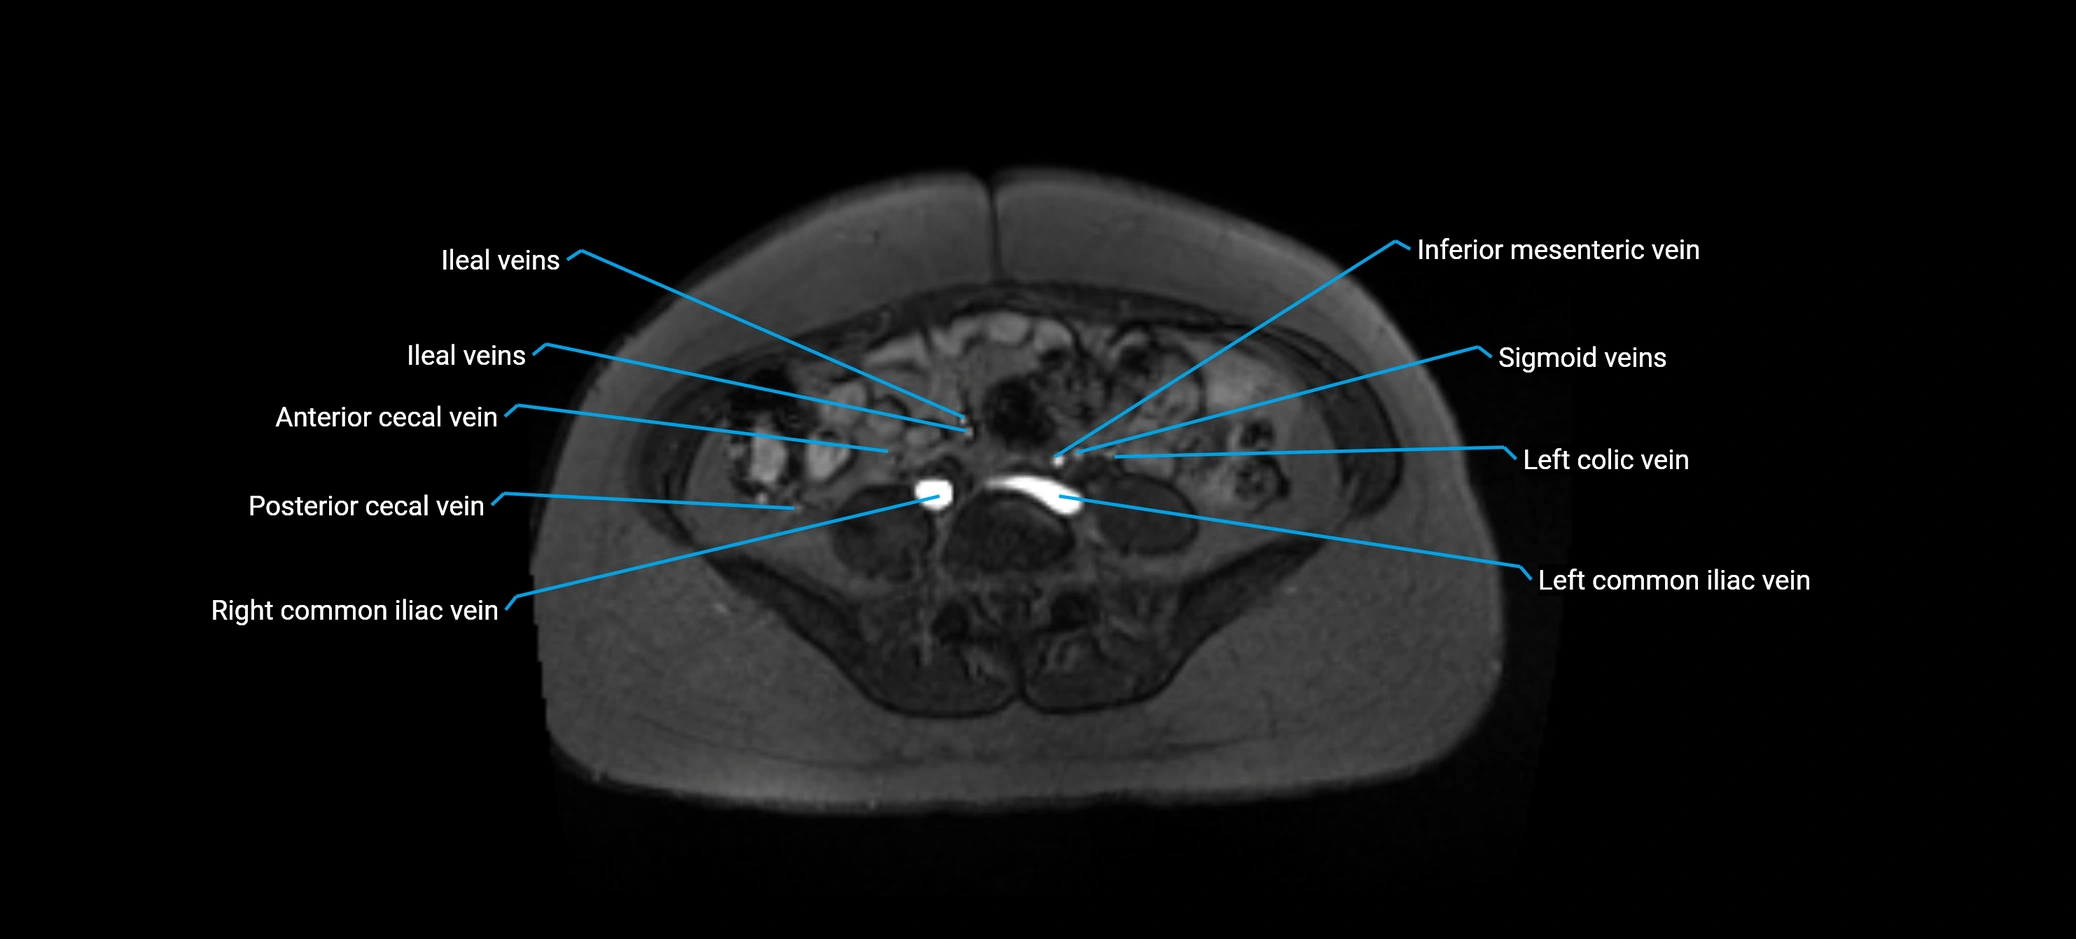

MRI image

image